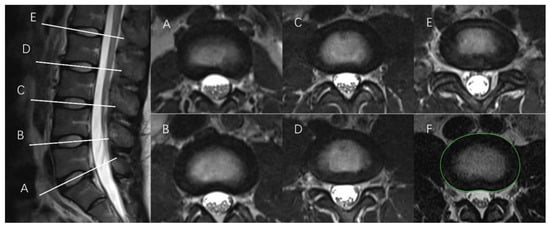

2.2.1. Tracing the IVD Contours

2.2.2. Tracing the NP Contours

- Region growing algorithm (RG)

- Select the initial pixels based on the nature of the image. In the case of this nucleus pulposus segmentation, because the boundary of the NP is blurred and the gray value near the boundary is significantly lower than that at the center of the NP, the point close to the boundary of the NP is selected as the seed pixel. This choice has shown better results in practice. The center of the NP is not the seed pixel because sometimes the NP contour cannot be obtained from the center of the NP.